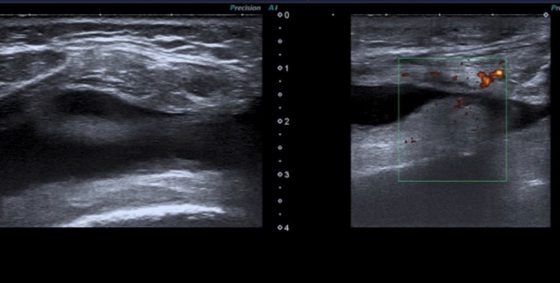

Ecografie Musculoscheletala la Clinica AlessMedical

Ecografia musculoscheletala este investigatia imagistică ce foloseste ultrasunetele pentru a vizualiza: articulatiile, muschii, tendoanele, ligamentele, bursele, oasele, cartilajul, nervii sau vasele de sange.

Examinarea ecografica este utila pentru medicul clinician in diagnosticul pacientilor cu afectiuni articulare, periarticulare sau musculare

Examinarea este sigura, nedureroasa, si poate fi repetata pentru a monitoriza evolutia leziunilor pacientului.

Beneficiul ecografiei musculoscheletale pe langa confirmarea diagnosticului, il reprezinta ecoghidare punctiilor, astfel medicul putand injecta medicamente cu precizie la nivelul structurilor anatomice.

Decelarea leziunilor anatomice permite aplicarea tintita a procedurilor de fizioterapie cu rezultate maximale pentru pacient.